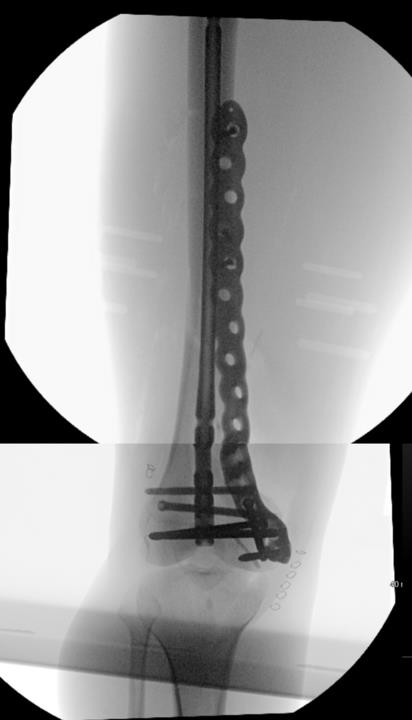

Summary Designed with SOMA (Stryker Orthopedics Modeling and Analytics) which includes a database with CT scans from hospitals across the world and state of the art algorithms that analyze shape variability, bone density, and implant fit Designed to link with the T2 Alpha Femur Retrograde Nail when using nail plate combination fixation Eight distal T20 screw holes, including 1 linking hole and 1 AP hole designed to capture Hoffa fragments Related Implants The Pangea® Femur Reconstruction System includes Lateral NPC Plate Medial NPC Plate (this topic) T2 Alpha™ Femur Retrograde Nailing System Design Tapered end allows for atraumatic submuscular insertion Staggered screw holes designed to enable surgeon to choose points of fixation and allows for placement of screws around an intramedullary implant or a prothesis AP hole screw hole trajectory that is designed to capture a "Hoffa Fragment" (Posterior Medial Condyle) Variable-angle screw holes circular universal holes accept non-locking screws, and locking screws within a 30° cone Proximal twist metadiaphyseal twist allows for screw placement anterior to posterior Linking hole designed to allow for seamless linking of the plate to a T2 Alpha Femur Retrograde Nail using an AlphaLink Dowel Indications Indications partial articular medial tibial plateau fractures medial plateau fragments in bicondylar tibial plateau fractures metaphyseal fractures epiphyseal fractures extra-articular proximal tibial fractures Contraindications active or suspected infection at the surgical site severe local inflammation around the operative area hypersensitivity or allergy to implant materials inadequate soft-tissue coverage over the implant Anatomy Osteology medial tibial plateau medial femoral condyle intercondylar eminence attachment point for cruciate ligaments tibial tuberosity insertion of the patellar tendon Muscles anteromedial tibia sartorius gracilis semitendinosus popliteus stabilizes and unlocks the knee Ligaments medial collateral ligament anterior cruciate ligament posterior cruciate ligament medial meniscus Approach Surgeons may use a standard medial, medial parapatellar, or medial subvastus approach to the distal medial femur Technical specifications Plate material type II anodized titanium (Ti6Al4V) Two plate lengths 155mm and 265mm Plate thickness 5mm Left and right anatomic options Screws Multiaxial locking 5.0 (14-120 mm) 4.0 (14-95mm) 5.0 (10-20mm) Cortex 4.5 (14-150mm) Cancellous 6.0 (20-150mm) 6.0 (30-150mm) 6.0 (45-150mm) Cable plug washer AlphaLink Dowel 50-90mm